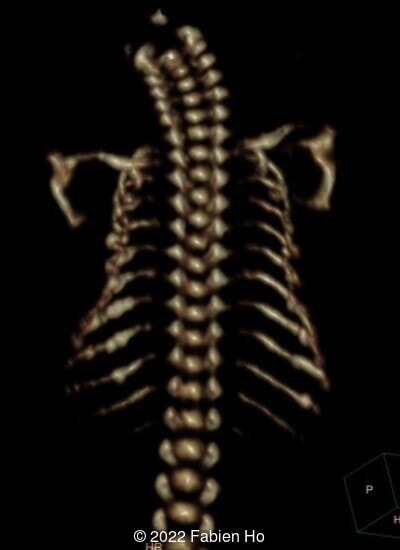

A CT scan was subsequently performed at 32 weeks gestation

The prenatal CT scan showed:

- Low bone density of skull and lower limbs

- Moderately narrowed and bell-shaped thorax

- Numerous bone calluses of the posterior arcs of the ribs

- Normal bone density of the spine

- No platyspondyly

- Very short long bones with curved femurs, tibias and fibulas. The curvature of the long bones reaches a 90° angle concerning for fracture. Upper limbs are moderately curved without fracture.